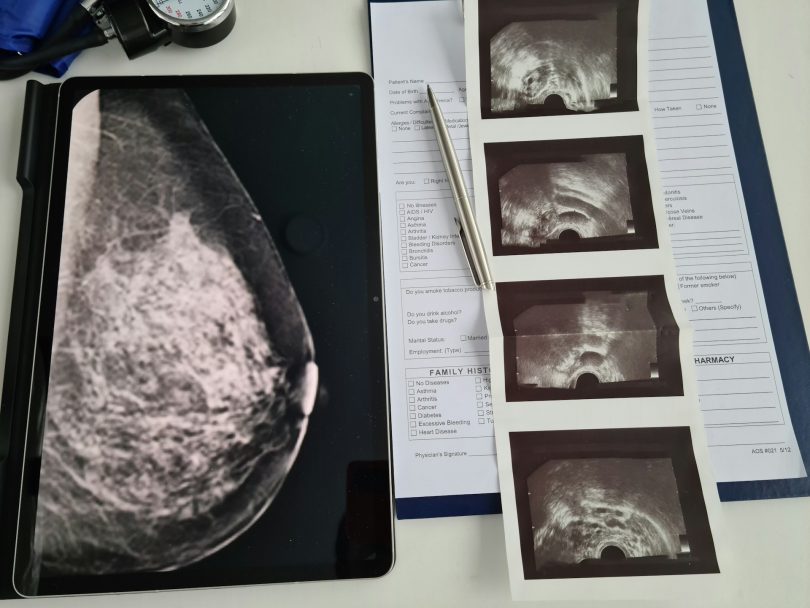

Research shows that Black women are often diagnosed at younger ages, at more advanced stages, and with more aggressive subtypes, which tends to grow and spread faster and has fewer treatment options. Other factors compound the problem: limited access to high-quality mammography centers, longer wait times for follow-up imaging or biopsy, under-insurance, and medical bias that can delay or downplay symptoms. In some cases, mammograms are interpreted without the benefit of newer technologies—like digital breast tomosynthesis (3D mammography) or even AI-assisted reading—that can better detect cancers in dense breast tissue, which is more common among younger women and Black women.

- Do I have dense breast tissue, and if so, how does that affect my risk or the accuracy of my mammogram?

Other manufacturers have also received clearances or approvals for AI tools that assist radiologists by marking suspicious areas, incorporating prior exams, and improving detection in dense breasts. For example, iCAD’s ProFound Detection v4.0 earned FDA clearance in 2024. It reports improvements in detecting cancers in dense tissue and finding smaller, aggressive cancers. Major imaging vendors (Hologic, ScreenPoint/Transpara, and others) also offer FDA-cleared AI solutions that are already being integrated into many mammography workflows.

- Better detection in dense breasts and younger patients. Black women are more likely than some other groups to be diagnosed with breast cancer at younger ages and with aggressive forms. Dense breast tissue can make cancers harder to see on traditional 2D mammograms. Newer AI tools that detect subtle patterns in dense tissue can help find cancers earlier, which may help reduce disparities in outcomes.